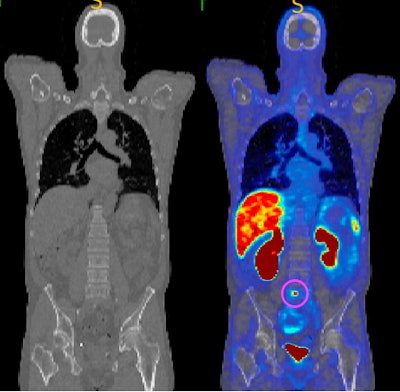

CT image (left) and gallium-68 (Ga-68) PSMA-11 PET/CT (right) showing an identified tumor circled in pink, which is not visible on the CT scan. This modality uses a radioactive tracer that targets tumors by binding to overexpressed PSMA in cancer cells. PSMA PET/CT offers high sensitivity and specificity, with studies showing it has higher detection rates compared to conventional imaging. All figures courtesy of Kaylee Molin, Martin Ebert et al and presented at the Royal Australian and New Zealand College of Radiologists (RANZCR) Annual Scientific Meeting (ASM).